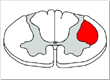

Upper Motor Neuron Lesion

The corticospinal tract has its main influence on the motor neurons that innervate the muscles of the distal extremities- the hand and the foot (motor neurons in the lateral part of the ventral horn). The corticospinal tract also (and this a key point) has collaterals that modulate and control the indirect brainstem motor centers so that we are not a stiff statue opposing gravity but rather we can move at will and have just the right amount of supporting tone. So when there is a lesion of the upper motor neuron (the UMN is the corticospinal tract and it’s collaterals to the brainstem motor nuclei) the clinical findings are a combination of the loss of direct effect of the corticospinal tract on the LMN plus the loss of control and modulation of the indirect brainstem motor control centers.

The clinical findings from a UMN lesion will include loss of distal extremity strength, dexterity and a Babinski sign (loss of direct corticospinal effect) plus increased tone, hyperreflexia, and the clasp-knife phenomenon (from loss of control of the indirect brainstem centers).

• An UMN lesion is on the opposite side of the clinical findings for a lesion above the decussation of the pyramids (where the corticospinal tracts cross) whereas it is on the same side as clinical findings if the lesion is in the spinal cord.